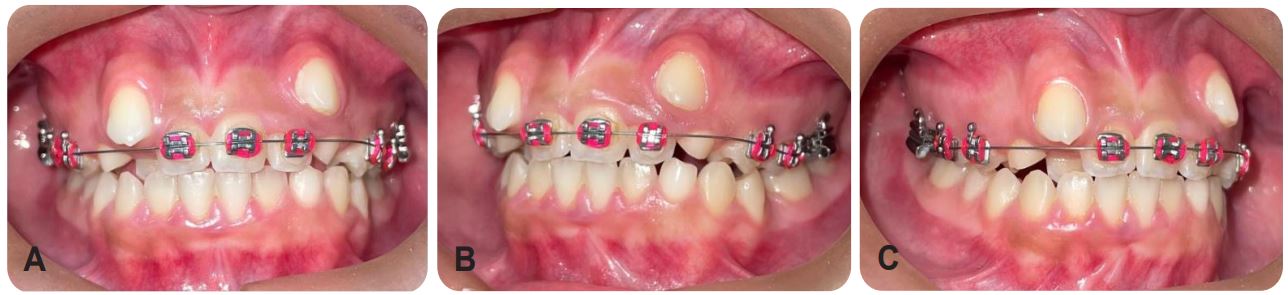

After analysis of the radiographic exams, a fixed mettalic Roth ligh from Morelli with Niti 12 wire was installed, as shown in (Figure 4). Subsequently, the orthodontic appliance was maintained with Niti 12 wire in the upper arch plus cementation of orthodontic bands in elements 16 and 26 (Figure 5), extraction of the two upper primary canines and lower left primary canine that were in prolonged retention and subsequent maintenance (Figure 6) presenting in A the third maintenance and in B was performed installation of the appliance in the lower arch plus maintenance with Niti wire 16 in the upper and lower arches, conjugated ligature from element 32 to 46, Morelli medium elastic chain from tooth 33 to 32 and bonding of teeth 13 and 23, and in C the fifth consultation with evolution of the lower Niti wire 18 with conjugated ligature of element 32 to 44, elastic chain on tooth 33 to 32, steel wire 16 in the upper arch, open spring between teeth 11 and 14 and between 22 and 24 and in D end E the subsequent maintenance until the present moment (Figure 7)

The results achieved with the treatment can be observed in Table 2, where there was an improvement in the quality of life of the patient in relation to the main complaint with the improvement of the aesthetics of the smile, in addition to that it can be observed dissolution of the dental crowding and better positioning of the canines in the dental arch. The patient is under follow-up and she and the person in charge are satisfied with the results achieved so far.

Figure 7: (a) Third visit, maintenance of the Niti 14 wire; (b) Fourth consultation, installation of the apparatus in the lower arch; (c) fifth consultation; (d) sixth consultation; (e) seventh maintenance; (f) Eighth maintenance and the last maintenances until the presente moment in G. (Source: The Authors, 2023).